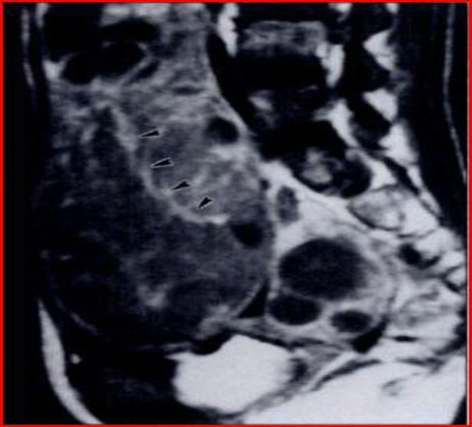

The microscopic examination of the mass reveals that the ovarian tissue is covered by a diffuse carpet of medium-sized cells, with some large cells (Figure 1) in foci, forming cords and trabeculae. The cells have scant cytoplasm, nuclei with aggregated chromatin, and numerous nucleoli (Figure 2). The immunohistochemical examination highlights the presence of cells positive for LCA and negative for cytokeratin, therefore the diagnosis of non-Hodgkin lymphoma with ovarian, omental and peritoneal involvement is made (most likely a diffuse large B-cell lymphoma). The patient undergoes a CT scan for a post-operative check-up which detects multiple lymph node enlargements in the common iliac, internal iliac and external iliac groups. Bone marrow biopsy reveals no marrow infiltrates. The patient is subjected to a chemotherapy protocol which includes 6 cycles of CHOP, but despite the therapy there is progression of the lymphoma with subsequent renal and splenic involvement.

Figure 1: The image shows an ovarian tissue rich in medium volume cells, with large cells in foci, which form cords and trabeculae.

Figure 2: The image shows cells with little cytoplasm, numerous nucleoli and nuclei with aggregated chromatin